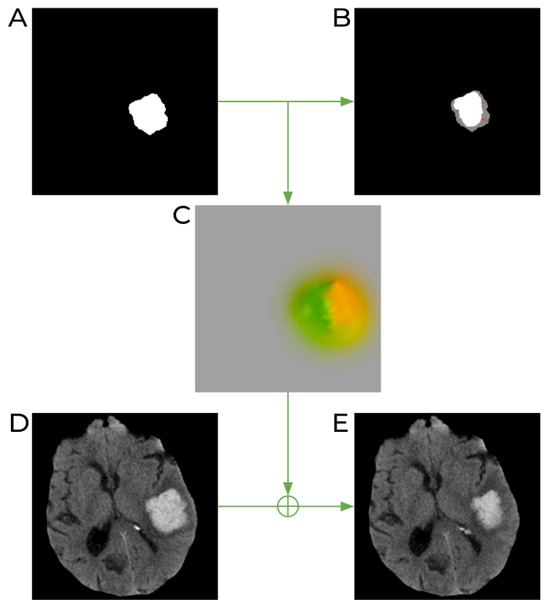

2.1.2. Synthetic Dataset Generation